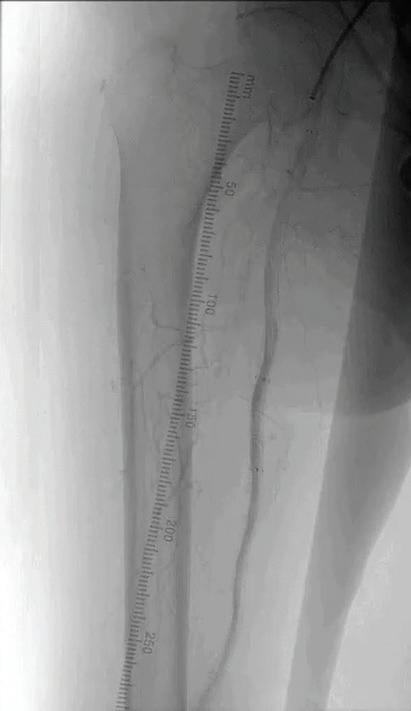

*All: drug, scaffold, resorbable excluding platinum markers.

1. Reintervention defined as CD-TLR. 2. Brian G. DeRubertis et al., Two-Year Outcomes of the LIFE-BTK Randomized Controlled Trial Evaluating the Esprit™ BTK Drug-eluting Resorbable Scaffold for Treatment of Infrapopliteal Lesions, VIVA 2024.

INDICATIONS The Esprit™ BTK Everolimus Eluting Resorbable Scaffold System is indicated for improving luminal diameter in infrapopliteal lesions in patients with chronic limb-threatening ischemia (CLTI) and total scaffolding length up to 170 mm with a reference vessel diameter of ≥ 2.5 mm and ≤ 4.00 mm.

MAT-2408411 v3.0 48% fewer patients require reinterventions through 2 years.1,2 Go above expectations with the only device that does it all for CLTI.*